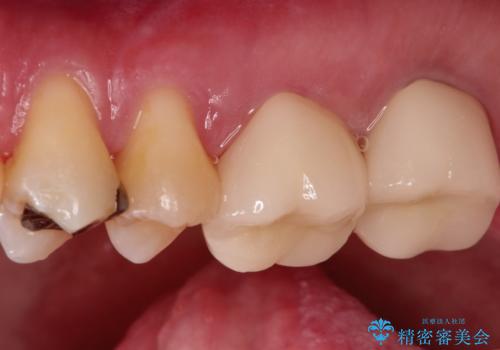

- 矯正の治療後に目立つ金歯を白くしたいとのことで治療することとなりました。

左上の奥歯に大きな金歯と、その後ろの歯が矯正治療用の仮歯が装着されていました。

これらの歯にオールセラミッククラウンを装着することとなりました。